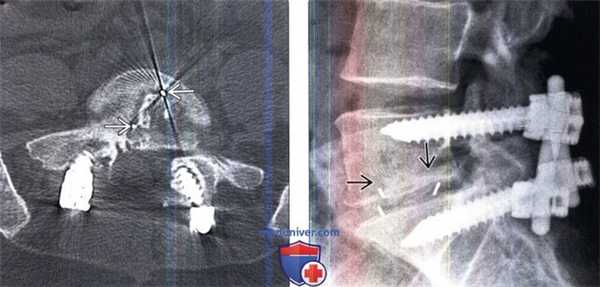

(Слева) Аксиальный КТ-срез: видны рентгенпозитивные метки рентгеннегативного межтелового спейсера (МС). Через 12 месяцев после операции межтеловое пространство уже должно быть заполнено зрелой трабекулярной костью. Если признаков костного блока к этому сроку нет, КТ можно повторить через 24 месяца после операции. Просветления вокруг границ межтелового спейсера (МС) свидетельствуют о несращении.

(Справа) Небольшие металлические маркеры в межтеловом пространстве позволяют идентифицировать положение рентгенонегативного (РЕЕК) межтелового спейсера. Маркер должен располагаться по меньшей мере в 2 мм кпереди от заднего края тел позвонков, только тогда можно быть уверенным, что край спейсера не пролабирует в спинномозговой канал.